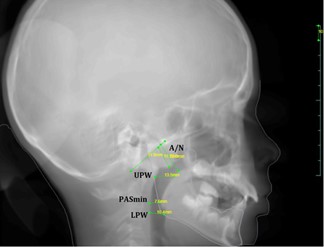

Все КЛКТ были занесены в список и пронумерованы. Затем все изображения были загружены в программное обеспечение Diagnocat (DC, ООО «Диагнокат», Москва, Россия), после чего для каждой томограммы был сформирован рентгенологический ортодонтический отчёт, ставший основой для автоматической оценки. Были проанализированы 3D-цветовая визуализация верхних дыхательных путей, их общий и минимальный объём. Те же КЛКТ были вручную проанализированы одним независимым стоматологом (оценщиком). С использованием ручной трассировки изображений в программе WEBCEPH на реконструированных боковых цефалограммах (RLCs) были определены и рассчитаны следующие параметры: UPW (верхняя глоточная ширина), LPW (нижняя глоточная ширина), PASmin (минимальная площадь дыхательного пути), коэффициент A/N.⁽¹⁷,¹⁸⁾

Среднее значение PASmin у всех пациентов составило 7,25 ± 1,2 мм, при этом в первой группе — 6,75 ± 2,6 мм, а во второй — 7,6 ± 2,77 мм (см. рисунок 1).

Рисунок 1. Измерения верхних дыхательных путей на RCL.

Согласно данным Hsu W.E. и соавт., минимальное пространство глотки (PASmin) представляет собой наиболее суженное расстояние в передне-заднем направлении в области верхних дыхательных путей. Это расстояние определяется как перпендикуляр, проведённый от задней стенки глотки до передней стенки⁽²¹⁾. В нашем исследовании PASmin также обозначалось как наиболее узкое переднезаднее расстояние верхних дыхательных путей. На двумерных реконструированных боковых цефалограммах (RLCs) PASmin также называют минимальным сагиттальным линейным размером (MSLD)⁽²²⁾.